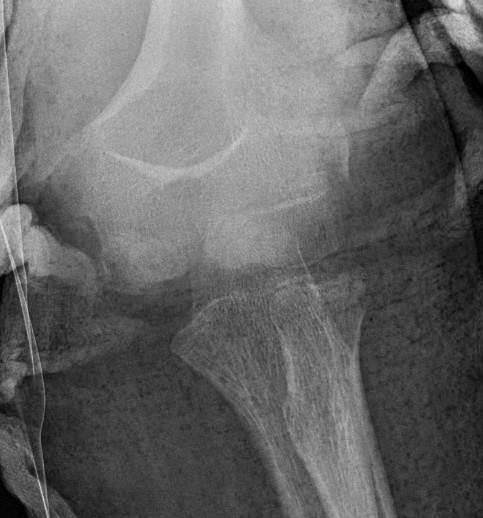

Incarcerated medial epicondyle fracture

Clinical / Xray

- absent medial epicondyle on xray / compare to contralateral side

- non congruent joint reduction

- consider CT / MRI / arthrogram / open exploration